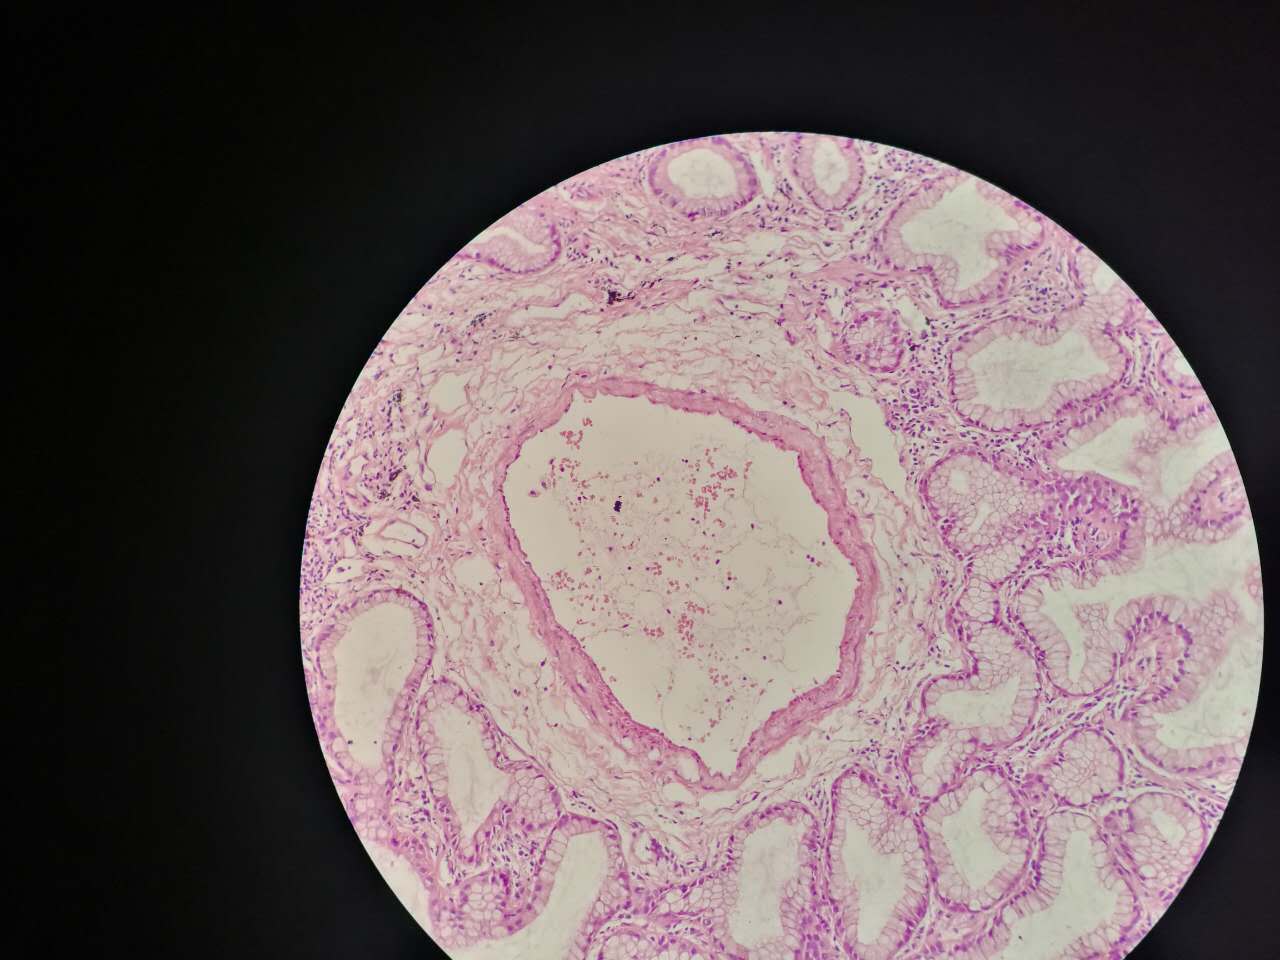

支气管粘膜鳞癌

结构紊乱,细胞异型

支气管鳞癌

复层排列,细胞有很多层

基底侧边界清楚

鳞癌生长,呈巢团状

巢团边界大多清楚

巢团可以很大,中央血供不足,就会坏死

中央红色的,有碎核

这个鳞癌不是早期

坏死也可以很大

较大的粉红区都是坏死,可以看出坏死是因为巢团大,中央坏死

这个下面的软骨说明了是大气管,中央型